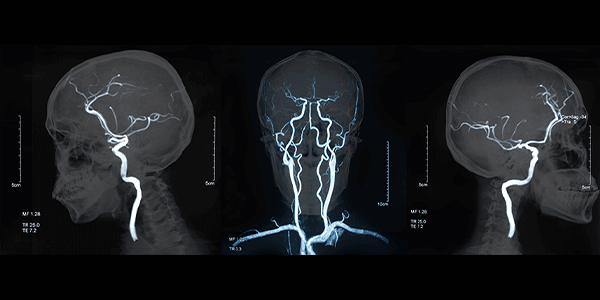

Serebral anjiyografi, farklı tekniklerle yapılabilir:

• Konvansiyonel anjiyografi: Yukarıda anlatılan standart yöntemdir.

• BT anjiyografi: Bilgisayarlı tomografi (BT) kullanılarak yapılan bir anjiyografi türüdür. Daha az invaziv bir yöntemdir ve genellikle konvansiyonel anjiyografi öncesinde ön değerlendirme amacıyla yapılır.

• MR anjiyografi: Manyetik rezonans görüntüleme (MR) kullanılarak yapılan bir anjiyografi türüdür. Kontrast madde kullanılmadan veya daha az kontrast madde kullanılarak yapılabilir.